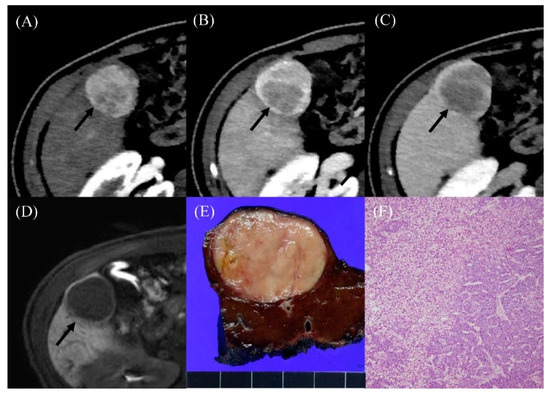

Histopathological Spectrum and Molecular Characterization of Liver Tumors in the Setting of Fontan-Associated Liver Disease

by Paola Francalanci, Isabella Giovannoni, Chantal Tancredi, Maria Giulia Gagliardi, Rosalinda Palmieri, Gianluca Brancaccio, Marco Spada, Giuseppe Maggiore, Andrea Pietrobattista, Lidia Monti, Aurora Castellano, Maria Cristina Giustiniani, Andrea Onetti Muda and Rita Alaggio

Cancers 2024, 16(2), 307; https://doi.org/10.3390/cancers16020307 - 11 Jan 2024

Purpose: Univentricular heart is corrected with the Fontan procedure (FP). In the long term, so-called Fontan-associated liver diseases (FALDs) can develop. The aim of this study is to analyze the molecular profile of FALDs. Methods: FALDs between January 1990 and December 2022 were [...] Read more.

Purpose: Univentricular heart is corrected with the Fontan procedure (FP). In the long term, so-called Fontan-associated liver diseases (FALDs) can develop. The aim of this study is to analyze the molecular profile of FALDs. Methods: FALDs between January 1990 and December 2022 were reviewed for histology and immunohistochemistry, laboratory data, and images. Targeted next generation sequencing (NGS), performed on the DNA and RNA of both neoplastic and non-lesional liver tissue, was applied. Results: A total of 31/208 nodules > 1 cm in diameter were identified on imaging, but a liver biopsy was available for five patient demonstrating the following: one hepatocellular adenoma (HA), two hepatocellular carcinomas (HCCs), one fibrolamellar carcinoma (FLC), and one intrahepatic cholangiocarcinoma (ICC). Molecular analysis showed a copy number alteration involving FGFR3 in three cases (two HCCs and one ICC) as well as one HCC with a hotspot mutation on the CTNNB1 and NRAS genes. Tumor mutational burden ranged from low to intermediate. A variant of uncertain significance in GNAS was present in two HCCs and in one ICC. The same molecular profile was observed in a non-lesional liver. A DNAJB1-PRKACA fusion was detected only in one FLC. Conclusions: Neoplastic FALDs show some unusual molecular profiles compared with non-Fontan ones. The presence of the same alterations in non-lesional cardiac cirrhosis could contribute to the development of FALD. Full article